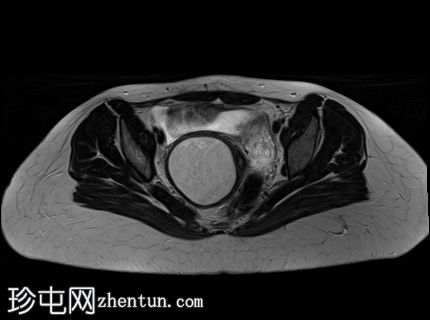

冠状位

T2加权像

子宫腔重复畸形,表现为两个子宫体和两个宫颈。

右侧宫颈和子宫腔明显扩张,内部血流信号显示中央狭窄,T1加权像呈高信号,T2加权像呈低信号,脂肪抑制序列图像上无信号下降,内部可见持续低信号灶。最大轴位和冠状位直径分别为约6.5 x 6.4 x 14.2 cm。可见该肿块向前压迫膀胱,向后推移右侧卵巢,并紧贴左侧宫颈。

双侧重复子宫腔的交界区完整,未见明显的肌层局灶性病变。左侧子宫内膜厚度正常。

可见两个阴道腔,共同远端开口长1.6厘米。

左侧卵巢囊肿最大轴径和头尾径分别约为5.7 x 4.3 x 5.5厘米,T2加权像呈高信号,T1加权像呈低信号。